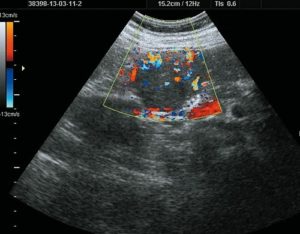

Основным достижением ЦДК в диагностике опухолевых процессов является визуализация и оценка кровотока новообразованных сосудов опухоли, которые имеют свои характерные особенности. Система васкуляризации опухоли представлена множеством мелких, очень тонких, аномальных по форме и расположению сосудов, хаотично разбросанных в пределах опухолевых тканей.

Кровоток в этих сосудах характеризуется крайне низким сосудистым сопротивлением, высокой скоростью и разнообразным направлением.

Особенности кровотока обусловлены трансформацией кровеносных сосудов в широкие капилляры или синусоиды, лишенные гладкой мускулатуры, наличием прекапиллярных дренажей и множественных артериовенозных анастомозов с очень низким сосудистым сопротивлением, которые обеспечивают высокую кинетическую энергию кровотока и широкую вариабельность его направления.

В результате многочисленных исследований Дж. Фолкмана было выявлено, что описанный тип кровообращения является особенностью первично злокачественных опухолей матки и яичников, что подтверждает гипотезу о том, что все быстрорастущие злокачественные новообразования продуцируют собственные сосуды для обеспечения дальнейшего роста.

Кровоток в доброкачественных опухолях имеет иной характер. Сосуды, участвующие в васкуляризации доброкачественных образований матки и яичников, являются непосредственным продолжением терминальных ветвей маточных и яичниковых артерий.

По мнению большинства авторов периферическая, с единичными сосудами, васкуляризация опухоли должна ассоциироваться с доброкачественностью, а наличие множественных сосудов в центральной части, на перегородках и в папиллярных разрастаниях является признаком злокачественноcти.

При пограничных кистомах и злокачественной трансформации яичников регистририруется неоваскуляризация: интенсивный центральный и периферический внутриопухолевый кровоток с низкими значениями индекса резистентности в новообразованных сосудах.

Цветовая допплерография позволяет выявить неоваскуляризацию опухоли: множественные цветовые сигналы от сосудов в пристеночных разрастаниях, на перегородках и в капсуле опухоли с низким уровнем резистентности (IR min – 0,40+0,07).

При эхографии серозных злокачественных опухолей обнаруживаются патологические образования больших размеров (13-20 см в диаметре), занимающие практически всю брюшную полость. Матка вовлекается в опухолевый конгломерат и в ряде случаев не визуализируется отдельно. Границы опухоли в большинстве случаев имеют бугристый контур и прослеживаются не на всем протяжении.

Муцинозные цистаденокарциномы характеризуются наличием множественных камер различного диаметра (1-4 см), некоторые из них заполнены мелкоячеистыми структурами средней эхогенности.

Возрастание ангиогенной активности и диффузно-высокая капиллярная плотность соответствует очагам пролиферации и малигнизации. Поэтому необходимо ориентироваться на минимальный индекс резистентности внутриопухолевых сосудов, как показатель, более точно отражающий процессы, происходящие в новообразовании.

Цветовое допплеровское картирование позволяет предоперационно, неинвазивно оценить и дифференцировать опухоли по степени изменений их сосудистой стенки, по локализации и количеству сосудов, являясь своеобразной мерой оценки злокачественности новообразований яичников. Сопоставление данных эхографии и допплерографии приводит к реальному повышению точности диагностики опухолевидных образований яичников.